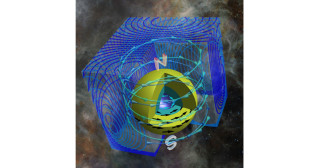

本プロジェクトおよび戦略的国際脳科学研究推進プログラムとの連携体制をもつ本研究グループは、世界最大級の霊長類脳標本コレクションを対象に、超高磁場MRI装置を用いて、脳標本を切り出すことなく神経線維の連絡性を可視化した拡散テンソル画像(diffusion tensor imaging; DTI画像)を撮像する顕微鏡的MRI技術を開発し、体重100gほどのマーモセットから体重38㎏のチンパンジーにまでわたる霊長類種の神経回路の多様性を全脳レベルで描出することに成功しました。本脳画像リポジトリは、今回の発表論文で第2フェーズへと入り、さらに、多様な霊長類の脳情報を包括的に提供することで、データ駆動型科学を通したヒト脳の特徴や精神・神経疾患の解明に貢献しています。

左から順に、ボリビアリスザル、ノドジロオマキザル、クロザル、チベットモンキー、チンパンジー